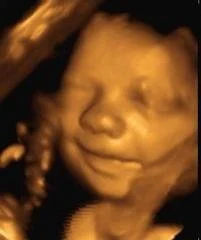

Our scans are designed to complement your routine NHS maternity care, offering additional reassurance and precious bonding moments throughout your pregnancy.

Please explore our full range of scans and packages below.